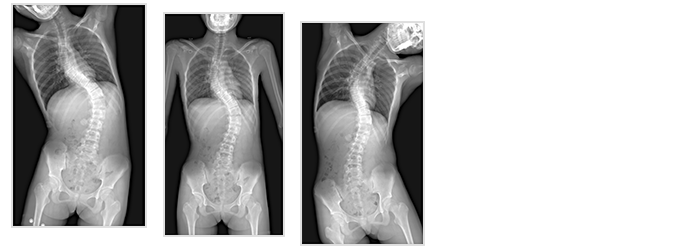

SLOT Advance, available on the Sonialvision G4 system, provides long leg and spine images.

Slot images are acquired using a narrow perpendicular X-ray beam tracking past the patient, producing a long image with almost no geometric distortion or magnification and very accurate measurements.

In Slot Advance, due to the perpendicular nature of the X-ray beam, there is practically no geometric distortion or elongation of the acquired image.

As such, the resultant Slot Advance images are very accurate in their anatomic representation.

- • Cobb Angle measurement.